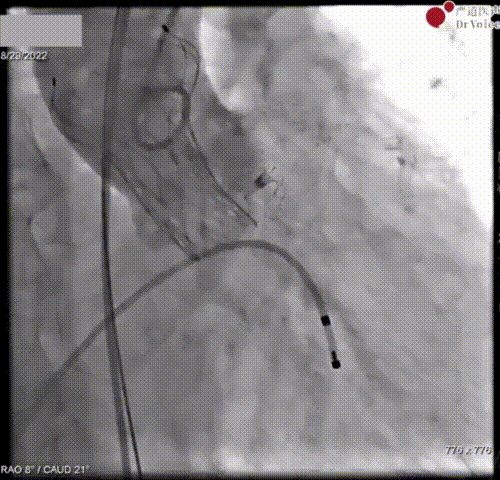

图7. 输送系统跨瓣

AV24瓣膜在瓣环下精准定位负位稳定释放。